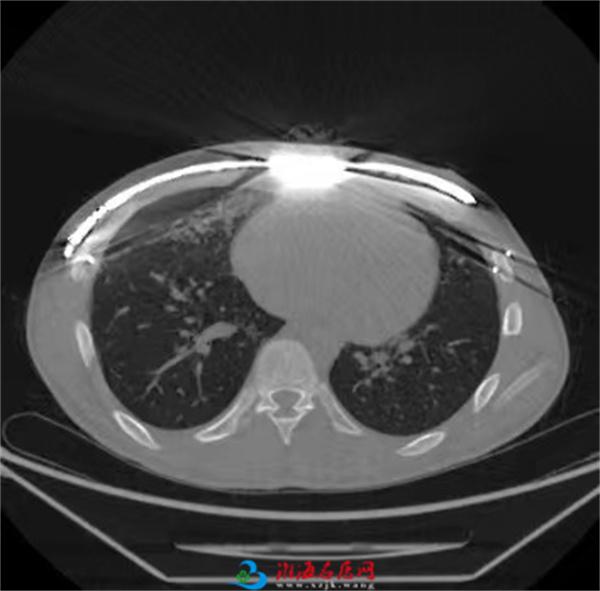

微创鸡胸反NUSS手术适应证:①CT Haller指数<2.30;②存在与鸡胸相关的心肺功能异常;③支具治疗无法耐受或失败,寻求微创手术治疗;④心理健康受到影响,寻求手术治疗。

胸部CT Haller指数测量